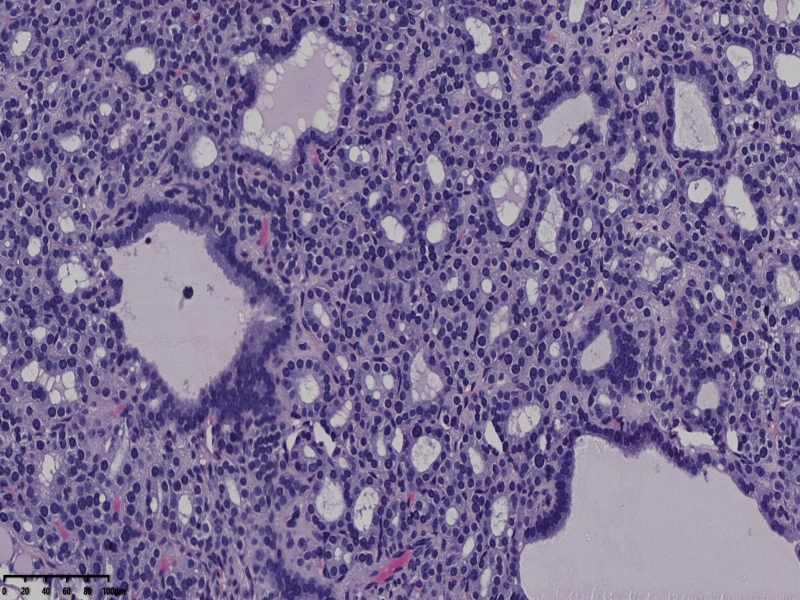

男、69、甲状腺左叶肿物,部分为囊性,囊内可见乳头状结构,上皮核重叠,没有核沟,没有毛玻璃样改变,没有核内假包涵体。255427

部分区域瘤组织与周围甲状腺组织分界明显,没有包膜样结构,滤泡结构为主,细胞异型明显。

会诊结果:(左叶甲状腺近峡部)甲状腺肿瘤,考虑为具有RAS核的乳头状癌,建议免疫组化及基因检测。